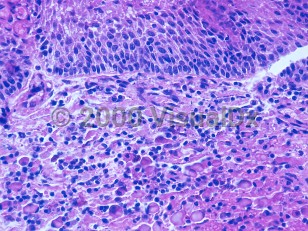

Plasma cell vulvitis, or Zoon disease, refers to an extremely rare skin condition where, secondary to inflammation, the vulva becomes irritated, leading to patient complaints of itching and discomfort.

The etiology is unknown but is thought to be related to viral elements, trauma, and/or chronic irritation. The condition tends to be diagnosed in postmenopausal patients.